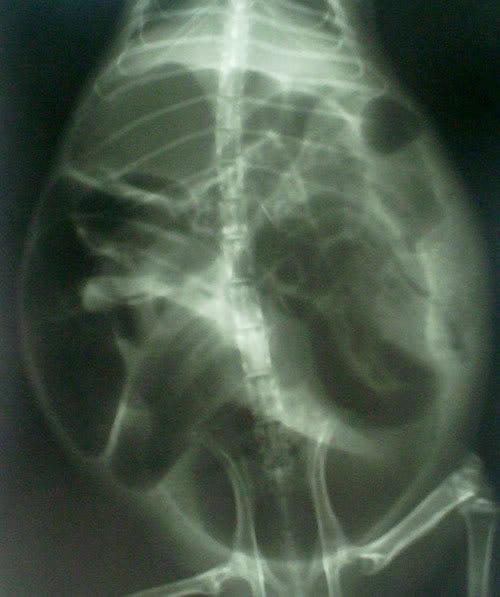

Ukoliko se plinovi ne riješe unutar par dana, potrebno je pronaći točan uzrok, pri čemu može pomoći RTG snimak.

Snimka normalnog abdomena:

Snimka plinovima ispunjenog abdomena: